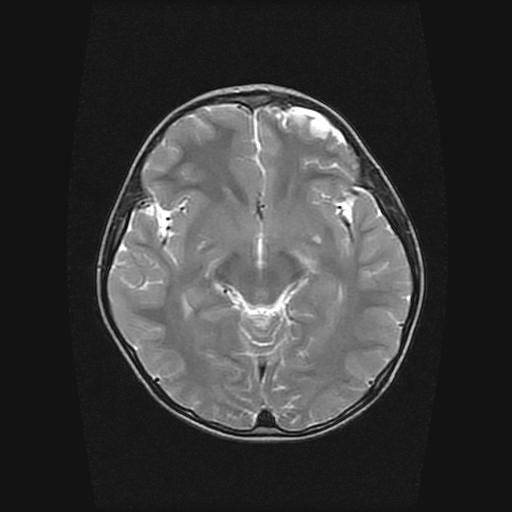

6岁小儿,左侧视神经瘤术后。现左侧视力减退。